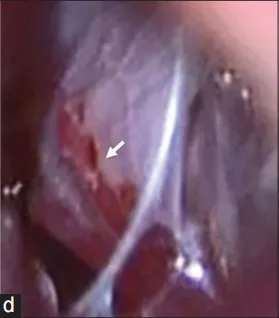

图4c:术中小脑后下动脉近端夹闭(箭头)。

图4d:术中右侧椎夹层动脉瘤及远端至脑干穿支(箭头)。